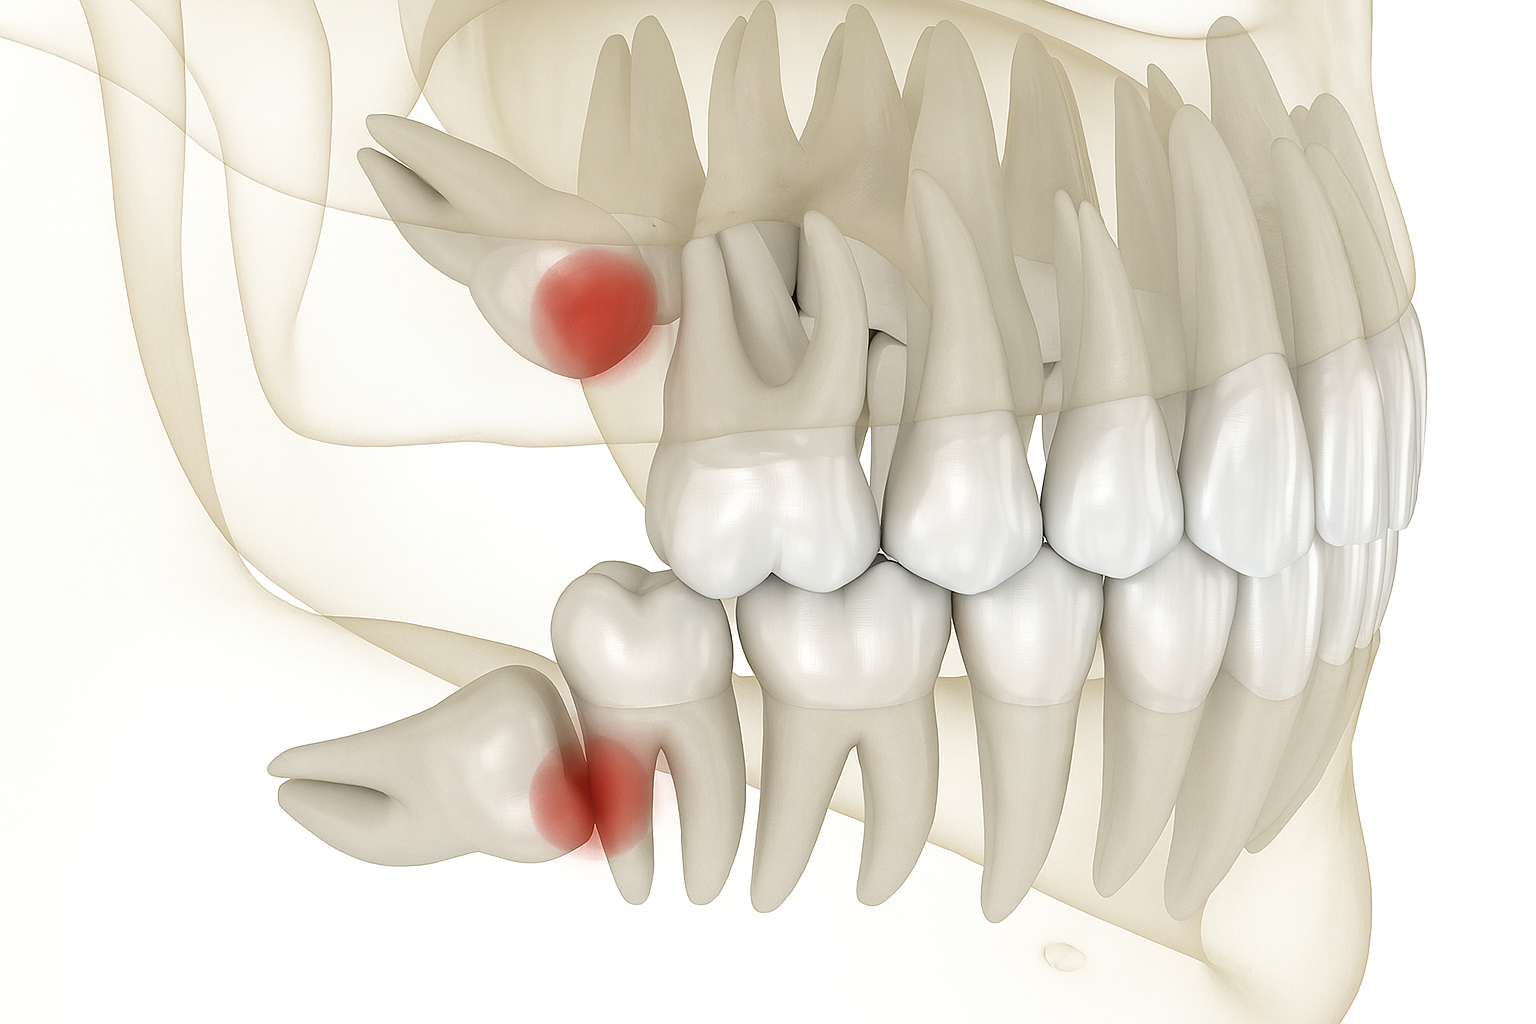

We offer a full range of dental services including braces, clear aligners (Invisalign alternatives), scaling & polishing, wisdom tooth removal, veneers, teeth whitening, fillings, and general dentistry. Using modern technology and gentle care, we aim to make every visit comfortable while helping you achieve optimal dental health and a confident smile.